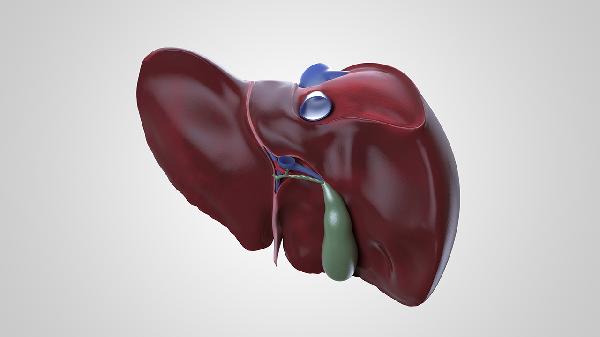

肝脏六大求救信号主要有皮肤黄染、食欲减退、疲乏无力、腹胀腹痛、尿液深黄、皮肤瘙痒。这些症状可能由肝炎、脂肪肝、肝硬化等疾病引起,建议及时就医检查肝功能。

腹胀腹痛多因肝脏肿大牵拉包膜或腹水形成所致,常见于肝硬化失代偿期。右上腹隐痛可能与胆囊疾病相关。治疗药物包括呋塞米片、螺内酯片、安络化纤丸等。饮食需限制钠盐摄入,避免产气食物,必要时需进行腹腔穿刺引流。

出现上述症状时应及时就医检查肝功能、腹部超声等项目。日常需保持规律作息,避免熬夜和过度劳累。饮食以清淡易消化为主,适量摄入优质蛋白如鱼肉、豆制品,限制高脂高糖食物。严格戒酒,避免使用损肝药物。定期进行肝功能复查,已有肝病患者需遵医嘱规范治疗。适当进行散步、太极拳等低强度运动,保持情绪稳定。